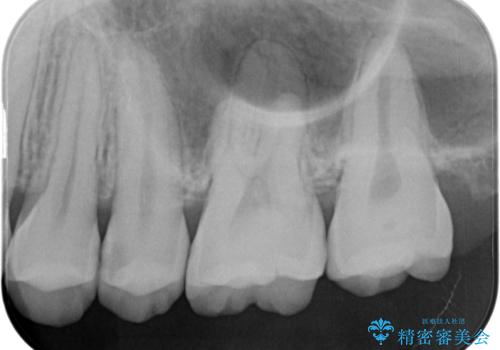

- 定期検診にてむし歯を認めたため、セラミックインレーにて修復を行いました。

e-max プレスインレーにて修復治療を行っているため適合性及び審美性の高い治療を行うことができます